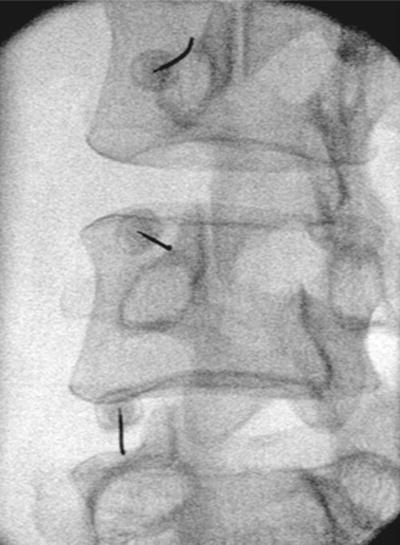

Πώς εκτελείται η διαδικασία νευρικού αποκλεισμού της άρθρωσης

Η διαδικασία μπορεί να διενεργηθεί στις αρθρώσεις του αυχένα, της ράχης και της μέσης. Με τον ασθενή σε πρηνή θέση και υπό τοπική αναισθησία εισάγεται μια βελόνα που υπό συνεχή ακτινοσκοπική καθοδήγηση φθάνει στους νευρικούς κλάδους της κάθε άρθρωσης. Μια μικρή ποσότητα αναισθητικού διαλύματος εγχέεται και αφαιρείται η βελόνα. Ο ασθενής αναπαύεται για 30 λεπτά και σε μία ώρα μπορεί να εξέλθει, μετά την αξιολόγησή του από τον θεράποντα ιατρό. Οι κίνδυνοι από τη διαδικασία είναι σπάνιοι.

Χορηγείται τοπική αναισθησία για να μουδιάσει το δέρμα. Ο ιατρός κάτω από ακτινοσκοπική καθοδήγηση, εισάγει μια λεπτή ειδική βελόνα που στοχεύει το σημείο διέλευσης του μέσου νευρικού κλάδου, το οποίο βρίσκεται στη συμβολή της άνω αρθρικής και της εγκάρσιας απόφυσης του σπονδύλου στην οσφυϊκή μοίρα.

Στην πορεία ακολουθεί κινητικός και αισθητικός ερεθισμός του νεύρου. Αυτό μπορεί να οδηγήσει σε μικρούς τοπικούς μυϊκούς σπασμούς και να προκαλέσει λίγο πόνο. Μόλις ελεγχθεί η σωστή τοποθέτηση της βελόνας, χορηγείται τοπικό αναισθητικό και ακολουθεί η θερμοκαυτηρίαση του νεύρου.